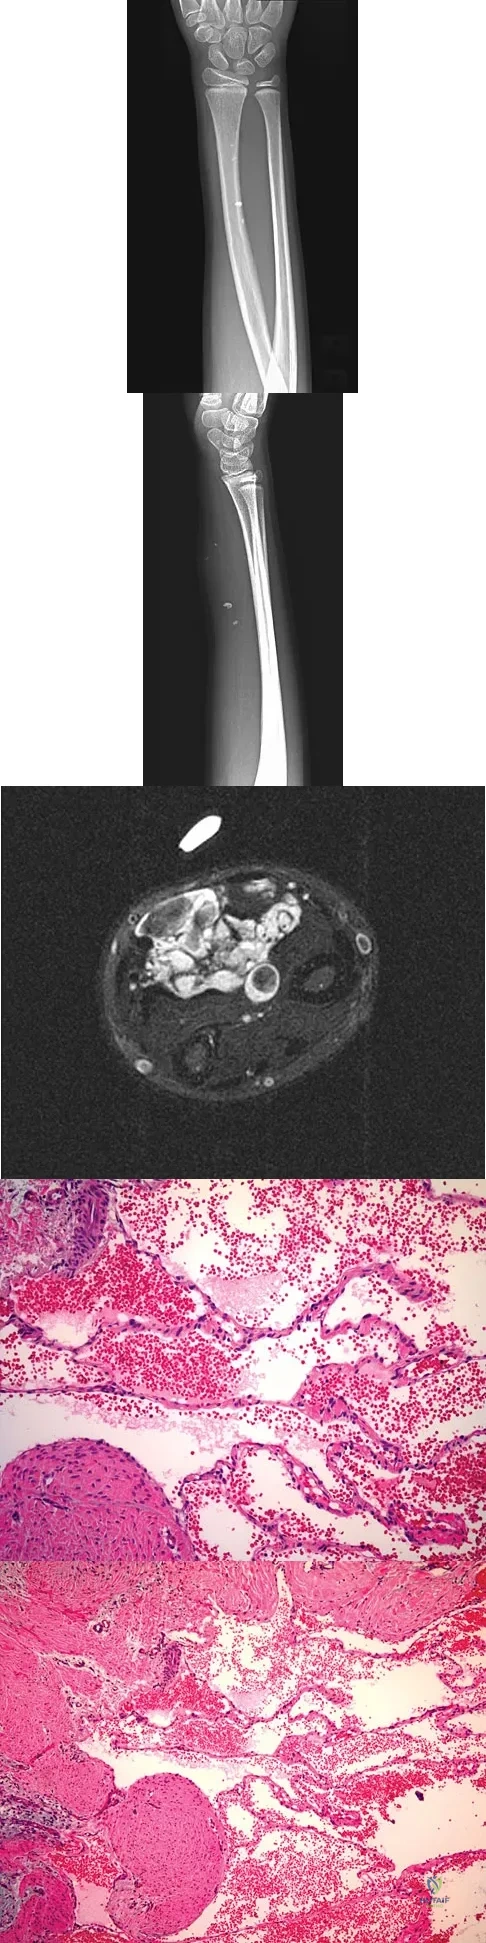

A 7-year-old girl has had a painful forearm for the past 2 months. Examination reveals fullness on the volar aspect of the forearm. Radiographs and an MRI scan are shown in Figures 42a through 42c. Biopsy specimens are shown in Figures 42d and 42e. What is the most likely diagnosis?

Explanation